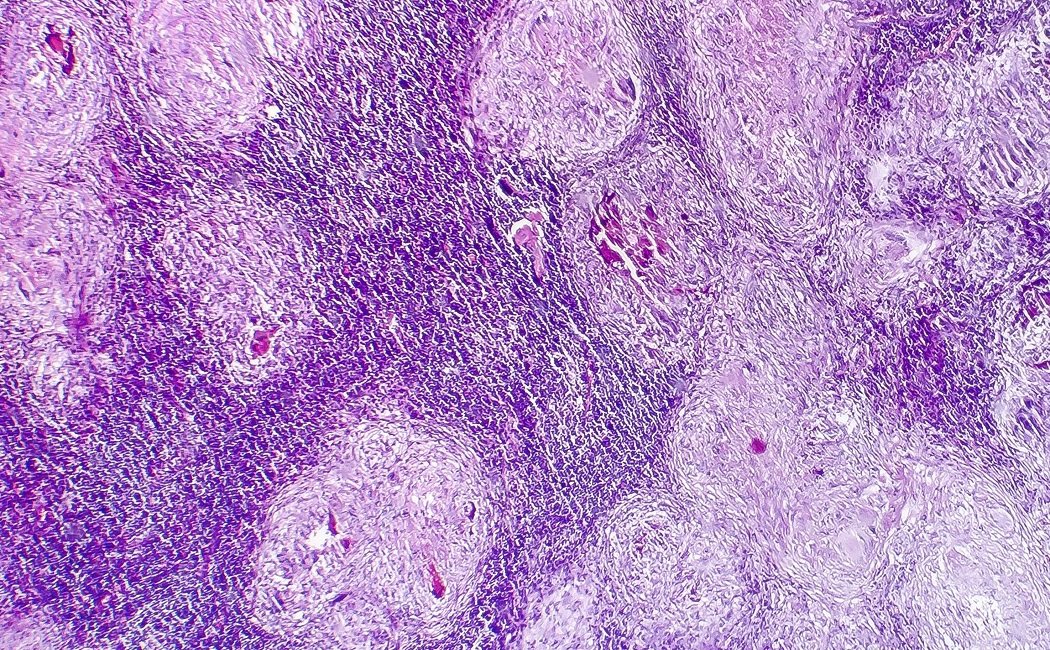

Son diferentes en apariencia

Bajo un microscopio, las células normales y las células cancerosas pueden verse muy diferentes. A diferencia de las células normales, las células cancerosas a menudo muestran una variabilidad mucho mayor en el tamaño de las células: algunas son más grandes de lo normal y otras son más pequeñas de lo normal. Además, las células cancerosas a menudo tienen una forma anormal, tanto de la célula como del núcleo (el "cerebro" de la célula). El núcleo aparece más grande y más oscuro que las células normales. La razón de la oscuridad es que el núcleo de las células cancerosas contiene un exceso de ADN. De cerca, las células cancerosas a menudo tienen un número anormal de cromosomas que se organizan de manera desorganizada.